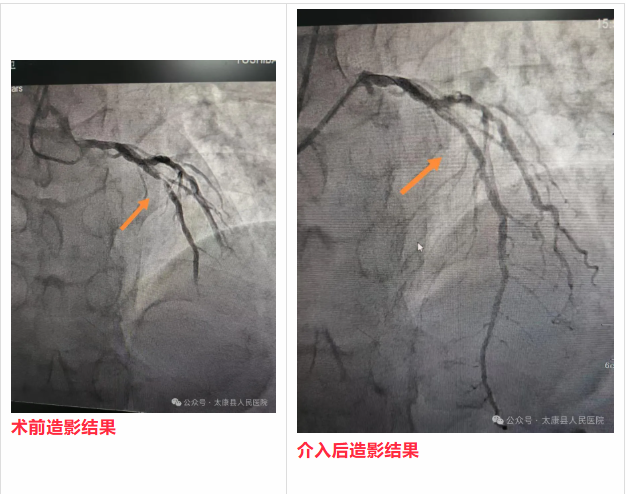

到院后,CCU主任陈永成带领介入团队已严阵以待。术中发现LAD中段狭窄约90%并血栓影,手术顺利开通了血管充分解除了血管狭窄,有效恢复了心肌供血。整个救治流程无缝衔接,大幅缩短了救治时间,最大程度降低了心肌坏死风险,为患者赢得了良好预后。